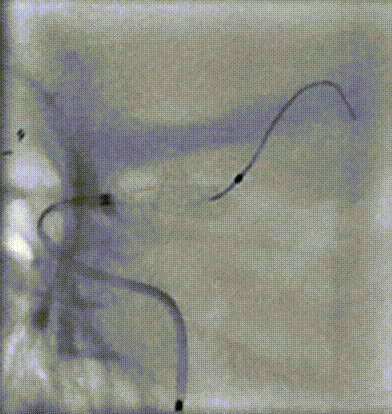

释放支架前段

释放支架后段

Evolve支架完全释放和按摩

导丝按摩

术后即刻